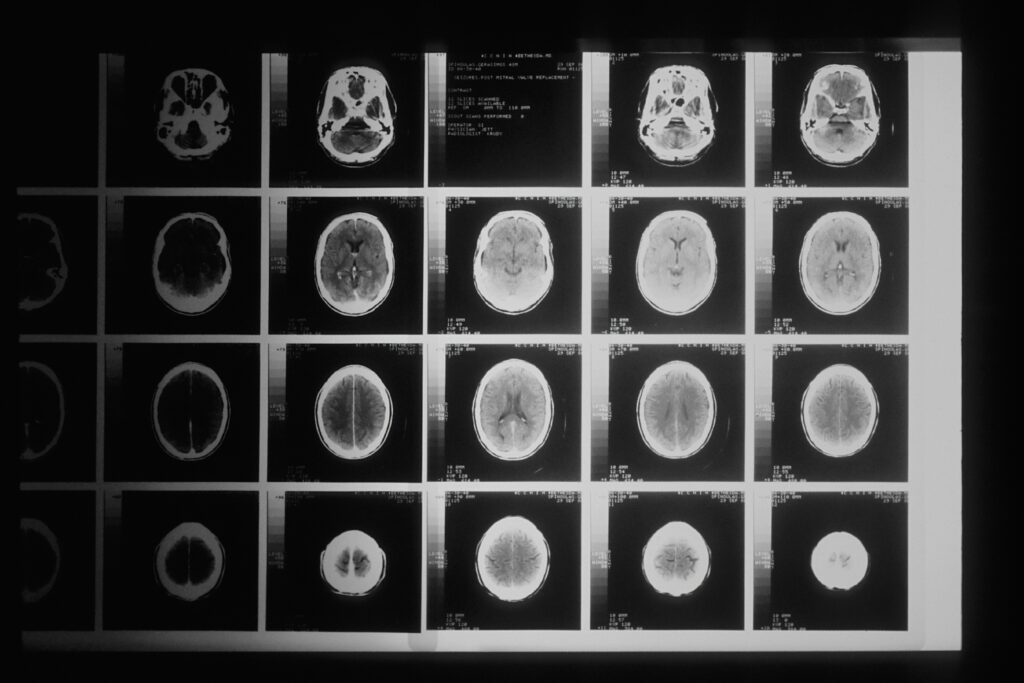

Digicyte is changing the game by developing a microscopic method that permits the analysis of fresh tumour biopsies in about 30 minutes. This is done without causing damage to the sample. After the analysis is complete, the sample can be used in standard diagnostic procedures. This tech works by combining infrared fluorescence microscopy, AI, and computer algorithms. What’s crucial here is an algorithm that reconstructs an H&E image from the infrared image. This is a standard format used by pathologists in diagnostics and provides them with a familiar diagnostic context, but in a time that was previously not possible.